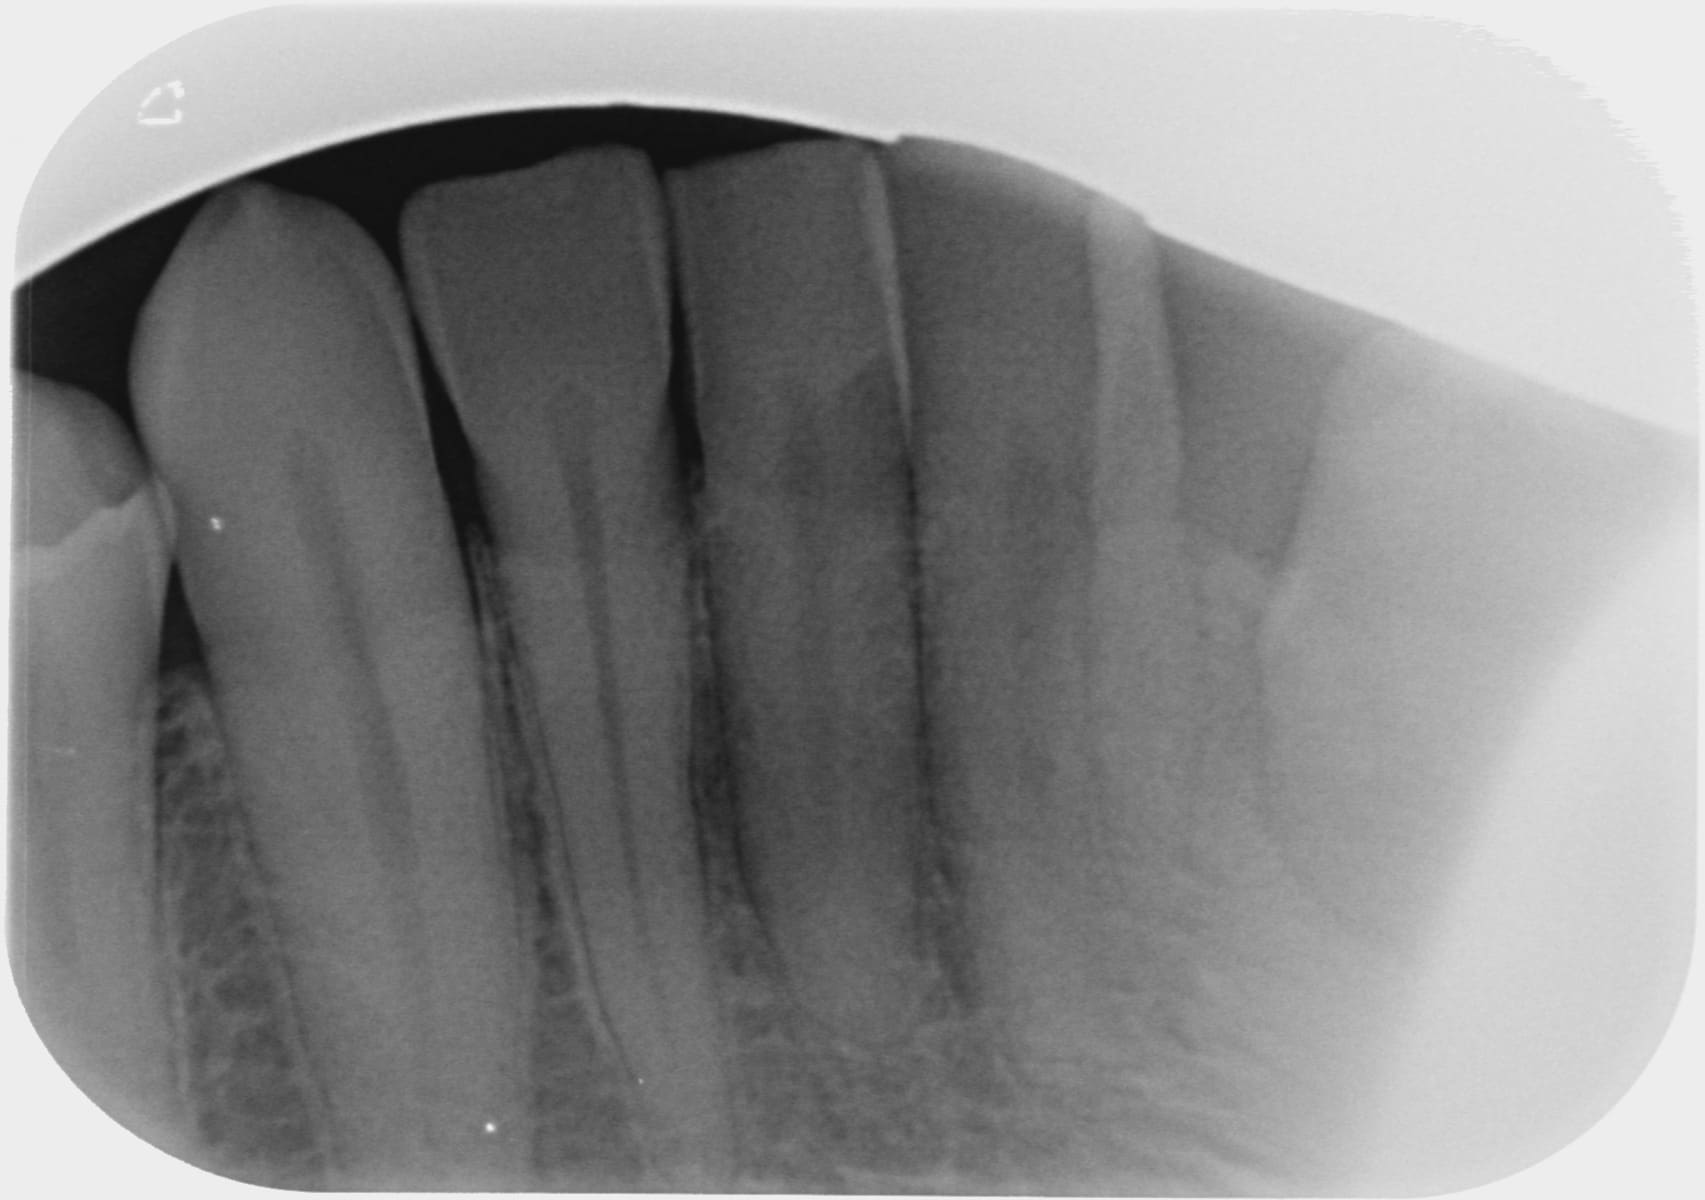

Actuellement la douleur tourne autour de la 42....voir radio en PJ

il n'y a rien, tests de vitalité fait...elle a réagit difficilement mais elle a réagit.

La radio est pas tres nette, mais je crois voir une carie en mesial de 42. Tu veux pas en faire une mieux, avec un angulateur?